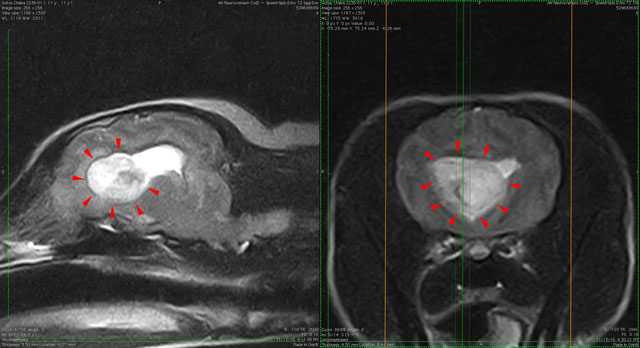

脳腫瘍 症例

11歳 ジャックラッセルテリア

ふらつきと姿勢維持困難を主訴に来院

側脳室前角から大脳鎌を超えて腫瘍が存在

神経膠腫を疑う